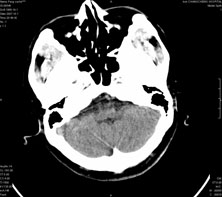

男,41岁,间断抽搐1小时,失神5分钟,bp130/90mmhg。低密度区ct值约16hu。

脑实质见多发散在的钙化点,左顶叶见一囊变灶,多考虑脑囊虫。

脑囊虫,部分囊内见头节。

脑实质见多发散在的钙化点,右颞、顶叶见囊性灶,考虑脑囊虫。